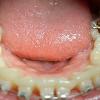

[오라픽스 치아교정 9 ] 고무줄 바꿔꼈어용

[오라픽스 치아교정 9 ] 고무줄 바꿔 꼇어용>_< 오랜만이에여 여러분~ 치과 갔다온지 ...

[오라픽스 치아교정 7] 다리가 생겼어용^0^

[오라픽스 치아교정 7 ] 다리가 생겼어용^0^ 삼주만이네요~요즘 너무 덥죠 ㅠ.ㅠ 모두 ...

[오라픽스 치아교정6] 발치♬

[오라픽스 치아교정 6 ] 발치 ♬ 여러분 오랜만이에요~ 발치를 한주에 한번씩 하다 보니...

[오라픽스 치아교정 5] 와이어 바꾸고 고무링 걸었습니다

[오라픽스 치아교정 5] 와이어 바꾸고 고무링 걸었습니다!!!!! 안녕하십니까^o^ 벌써 ...

[오라픽스 치아 교정 4] 와이어 교체하구 파워체인 달앗쪄여~

[오라픽스 치아 교정 4] 와이어 교체하구 파워체인 달았쪄여~ 아 정말 오랜만에 글쓰는...

[오라픽스 치아교정 3] 와이어 바꿔꼈어요♪♪♪

[오라픽스 치아교정 3] 와이어 바꿔꼈어요♪♪♪ 후아~~이벤트당첨으로 루벤칫솔 후기랑 ...

[오라픽스 치아교정 1] 교정 장치를 달았습니당*^^*

[오라픽스 치아교정 1] 교정 장치를 달았습니당*^^* 안녕하세요. 오라픽스로 치아 교정...